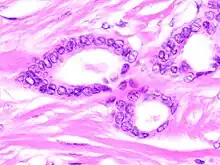

Tubular carcinomas are generally around 1 cm. or smaller, and are made up of tubules. They are usually low-grade.[2] Elastosis has been noted as common but is not present in all cases.[11]

- 1 2 Image by Mikael Häggström, MD. Reference for typical features: Pragya Virendrakumar Jain, M.D., Julie M. Jorns, M.D. "Breast - Other invasive carcinoma subtypes, WHO classified - Tubular". Pathology Outlines.

- 1 2 Stavros, A. Thomas (2004). Rapp, Cynthia L.; Parker, Steve H. (eds.). Breast Ultrasound. Lippincott Williams & Wilkins. pp. 647–649. ISBN 978-0-397-51624-7. OCLC 1065689596. p. 649:

A highly differentiated invasive carcinoma that forms well-defined tubules (containing epithelium, but no myoepithelium) and that have abundant desmoplastic fibrous stromal reaction between the tubules.